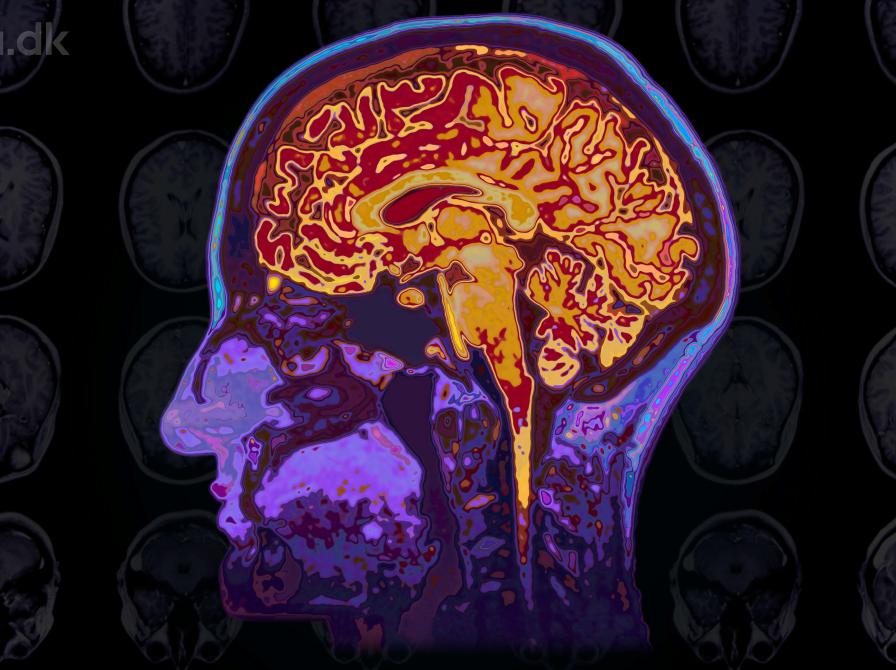

Hvordan reagerer vores hjerner på for eksempel natur, mad og musik

Hjerneskanninger og computermodellering bidrager til nye indsigter i, hvordan nydelse, begær og meningsfylde er indrettet i hjernen, og hvordan vores livskvalitet kan forbedres med dem.